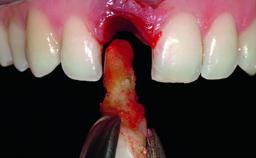

A 36-year-old male patient with a compromised maxillary central incisor was referred by his general dentist for consultation. The patient’s chief complaints were the gradual debonding of a temporary crown on the right central incisor and unsatisfactory esthetics due to an increasing diastema between the right central and lateral incisors. The patient reported a traumatic event some years previously, when a crown had been placed after root-canal treatment. The referring dentist wanted to provide a new crown restoration, but was concerned about the condition of the residual root. Anamnesis was negative for any other dental or periodontal pathology in the remaining dentition. The patient reported taking no medications: He was a smoker (10 to 15 cigs/day) and had realistic esthetic expectations.

Bone Augmentation Horizontal|Simultaneous|Staged

Augmentation Materials Xenogenous|Membrane

Bone Volume Deficient horizontally, requiring prior grafting